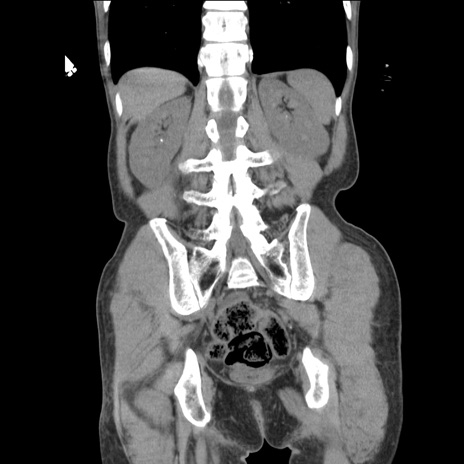

症例11(冠状断像)

【症例】 60歳代男性

【主訴】 下腹部痛

【現病歴】 本日夜中より下腹部痛の症状認め、受診。

【既往歴】 膀胱癌(膀胱全摘+尿管皮膚瘻術) 、胃癌術後

【身体所見】 BT 35.3℃、PR 58/min、BP 136/98mHg、腹部平坦、軟、腸蠕動音±、ストマ留置あり、左上腹部~正中部に圧痛あり、反跳痛なし。

【データ】WBC 5100、CRP0.01